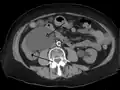

Peripelvic renal cysts may look like hydronephrosis on non-contrast CT (left image). However, CT urography (at right) reveals non-dilated calyces and pelvises.